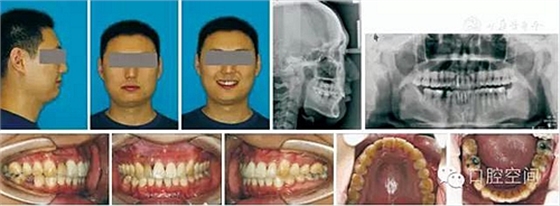

30歲男性患者,由于下前牙經(jīng)常咬傷上牙腭側(cè)牙齦,要求矯正調(diào)整咬合關(guān)系。上頜粘接直絲弓矯治器2個月后,下頜開始固定矯治,排齊牙列。4個月后下頜更換至0.018英寸鎳鈦絲,在下頜中切牙之間前庭溝處,局麻下切開黏膜,正中聯(lián)合部位植入一顆微螺釘(1.6 mm×9 mm,慈北醫(yī)療器械有限公司)。以直徑0.30 mm結(jié)扎絲連接微螺釘頭部,并穿出黏膜形成牽引鉤形狀。一周后開始加力,以微螺釘種植體支抗行閉合式牽引壓低下頜切牙。10個月后下切牙壓低良好,前牙覆頜正常,去除支抗螺釘。固定矯治20個月后,進入保持階段?;颊呙骖M像、X線片及頭影測量重疊圖見圖4,圖5,圖6,圖7,圖8,圖9,治療前后頭影測量結(jié)果見表2。

圖4病例1治療前面像及X線片

圖5病例1治療中像,以微螺釘支抗閉合式牽引開始壓低下切牙